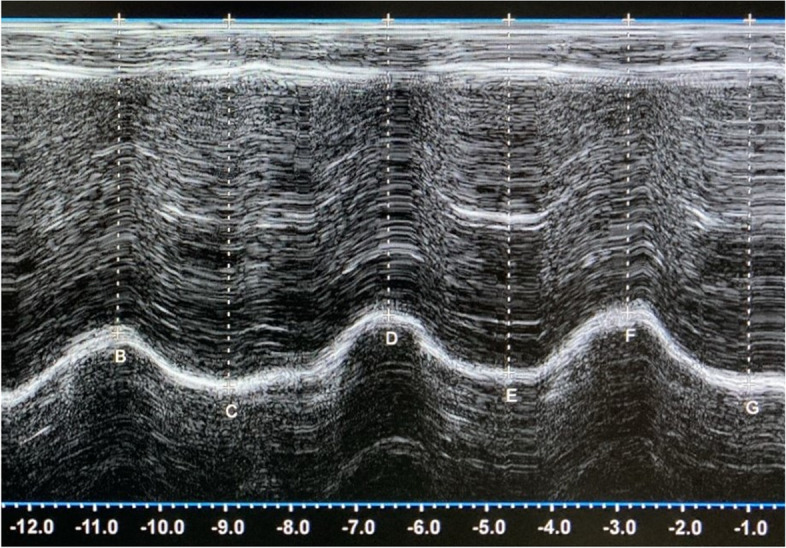

In the M-mode trace, the diaphragm is shown as an echogenic line. The position of the diaphragm was determined as the distance between the inspiratory peak and the expiratory peak of the curve from the probe (Fig. 1). This distance was measured vertically from the center of the echogenic line to the baseline. Excursions were then calculated as the difference between the end-expiratory and end-inspiratory positions. All ultrasonographic measurements were reported in millimeters.

Fig. 1.

M-mode ultrasonographic image of the diaphragm motion. The cursor is placed on the peak of the curve at the end-inspiratory (upper peaks B, D, F) and end-expiratory (lower peaks C, E, G) phase of breathing with a vertical line to the baseline